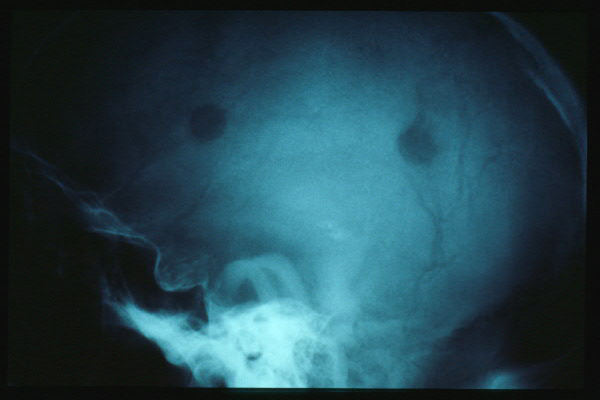

Hernia de hiato gigante.

Hernia de hiato por deslizamiento al TGED.

Hernia de hiato por deslizamiento al TEGD.

Hernia de hiato.